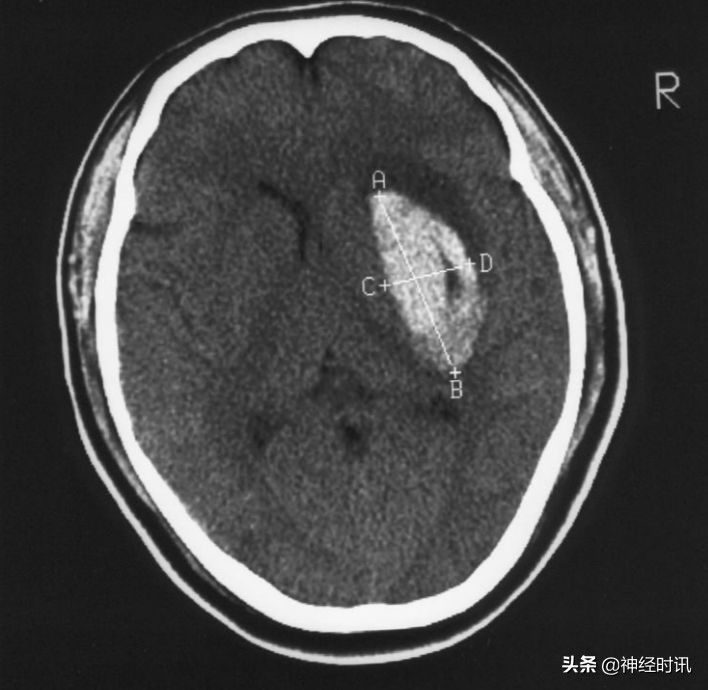

头颅CT: 是确诊脑出血的首选检查

① 急性期CT显示高密度影。

② 可显示出血部位,出血量,中线移位,有否破入蛛网膜下腔及脑室,有助于指导治疗和判断预后。

③ 血肿量计算法,血肿量=长×宽×层面×π/6